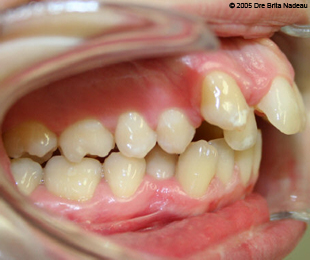

Marie-Hélène Cyr - Right lateral intraoral view - Before orthodontic treatments and orthognathic surgeries (November 24, 2005)

November 24, 2005 - The class II malocclusion is very visible on this right lateral view.